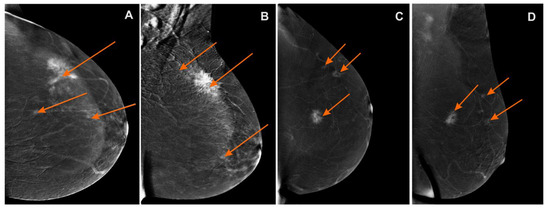

Figure 3. Contrast-enhanced spectral mammography (CESM)subtraction images: (A) craniocaudal (CC) and (B) mediolateral oblique (MLO) views—irregular mass with heterogeneous enhancement and long spiculated mass BI-RADS 6. Numerous enhanced small foci are noted in left breast BI-RADS 4 (orange arrows); (C) craniocaudal (CC) and (D) mediolateral oblique (MLO) views—irregular mass with heterogeneous enhancement and long spiculated mass BI-RADS 6. Additional enhanced small foci are noted in the left breast in superior-outer quadrant BI-RADS 4 (orange arrows).